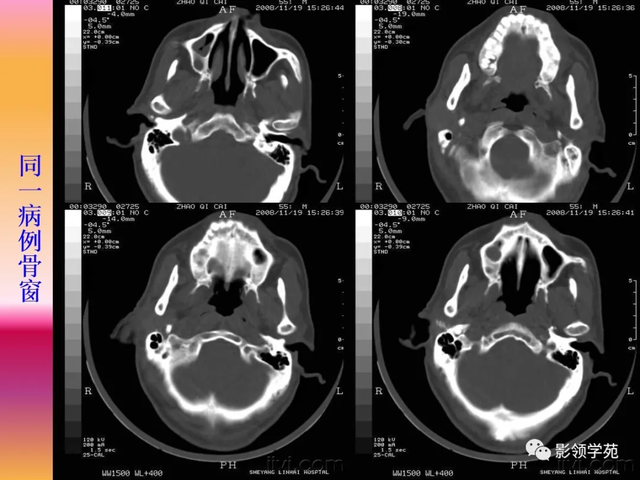

腮腺炎的CT体现及其病理基础

CT体现可归纳综合为3种类型:

(1)双侧或单侧腮腺弥漫性增大,密度匀称 增高,与周围结构分界清晰 。

(2)单侧腮腺弥漫性增大,密度不匀称 ,边缘模糊,与咬肌分界欠清晰,增强后不匀称 强化。

(3)单侧腮腺内局限性高密度影,密度较匀称 ,边缘模糊,增强后界线 稍清晰。